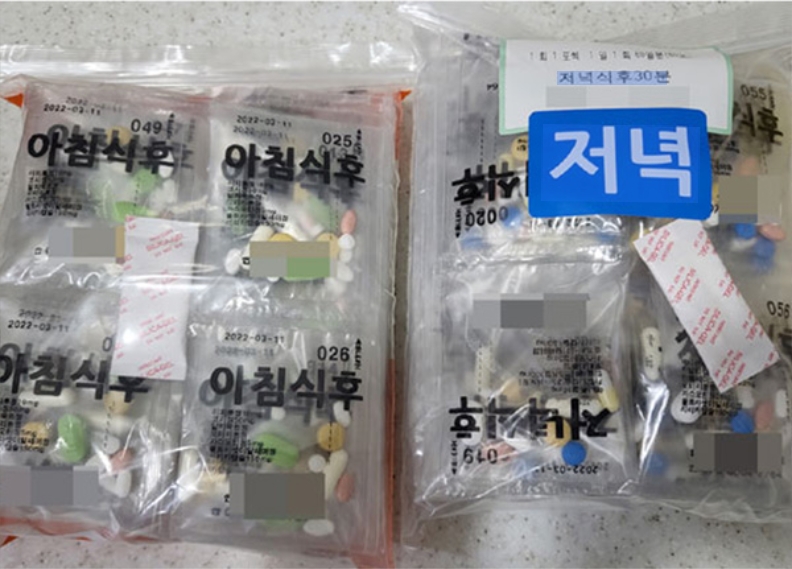

체질별 다이어트 처방약